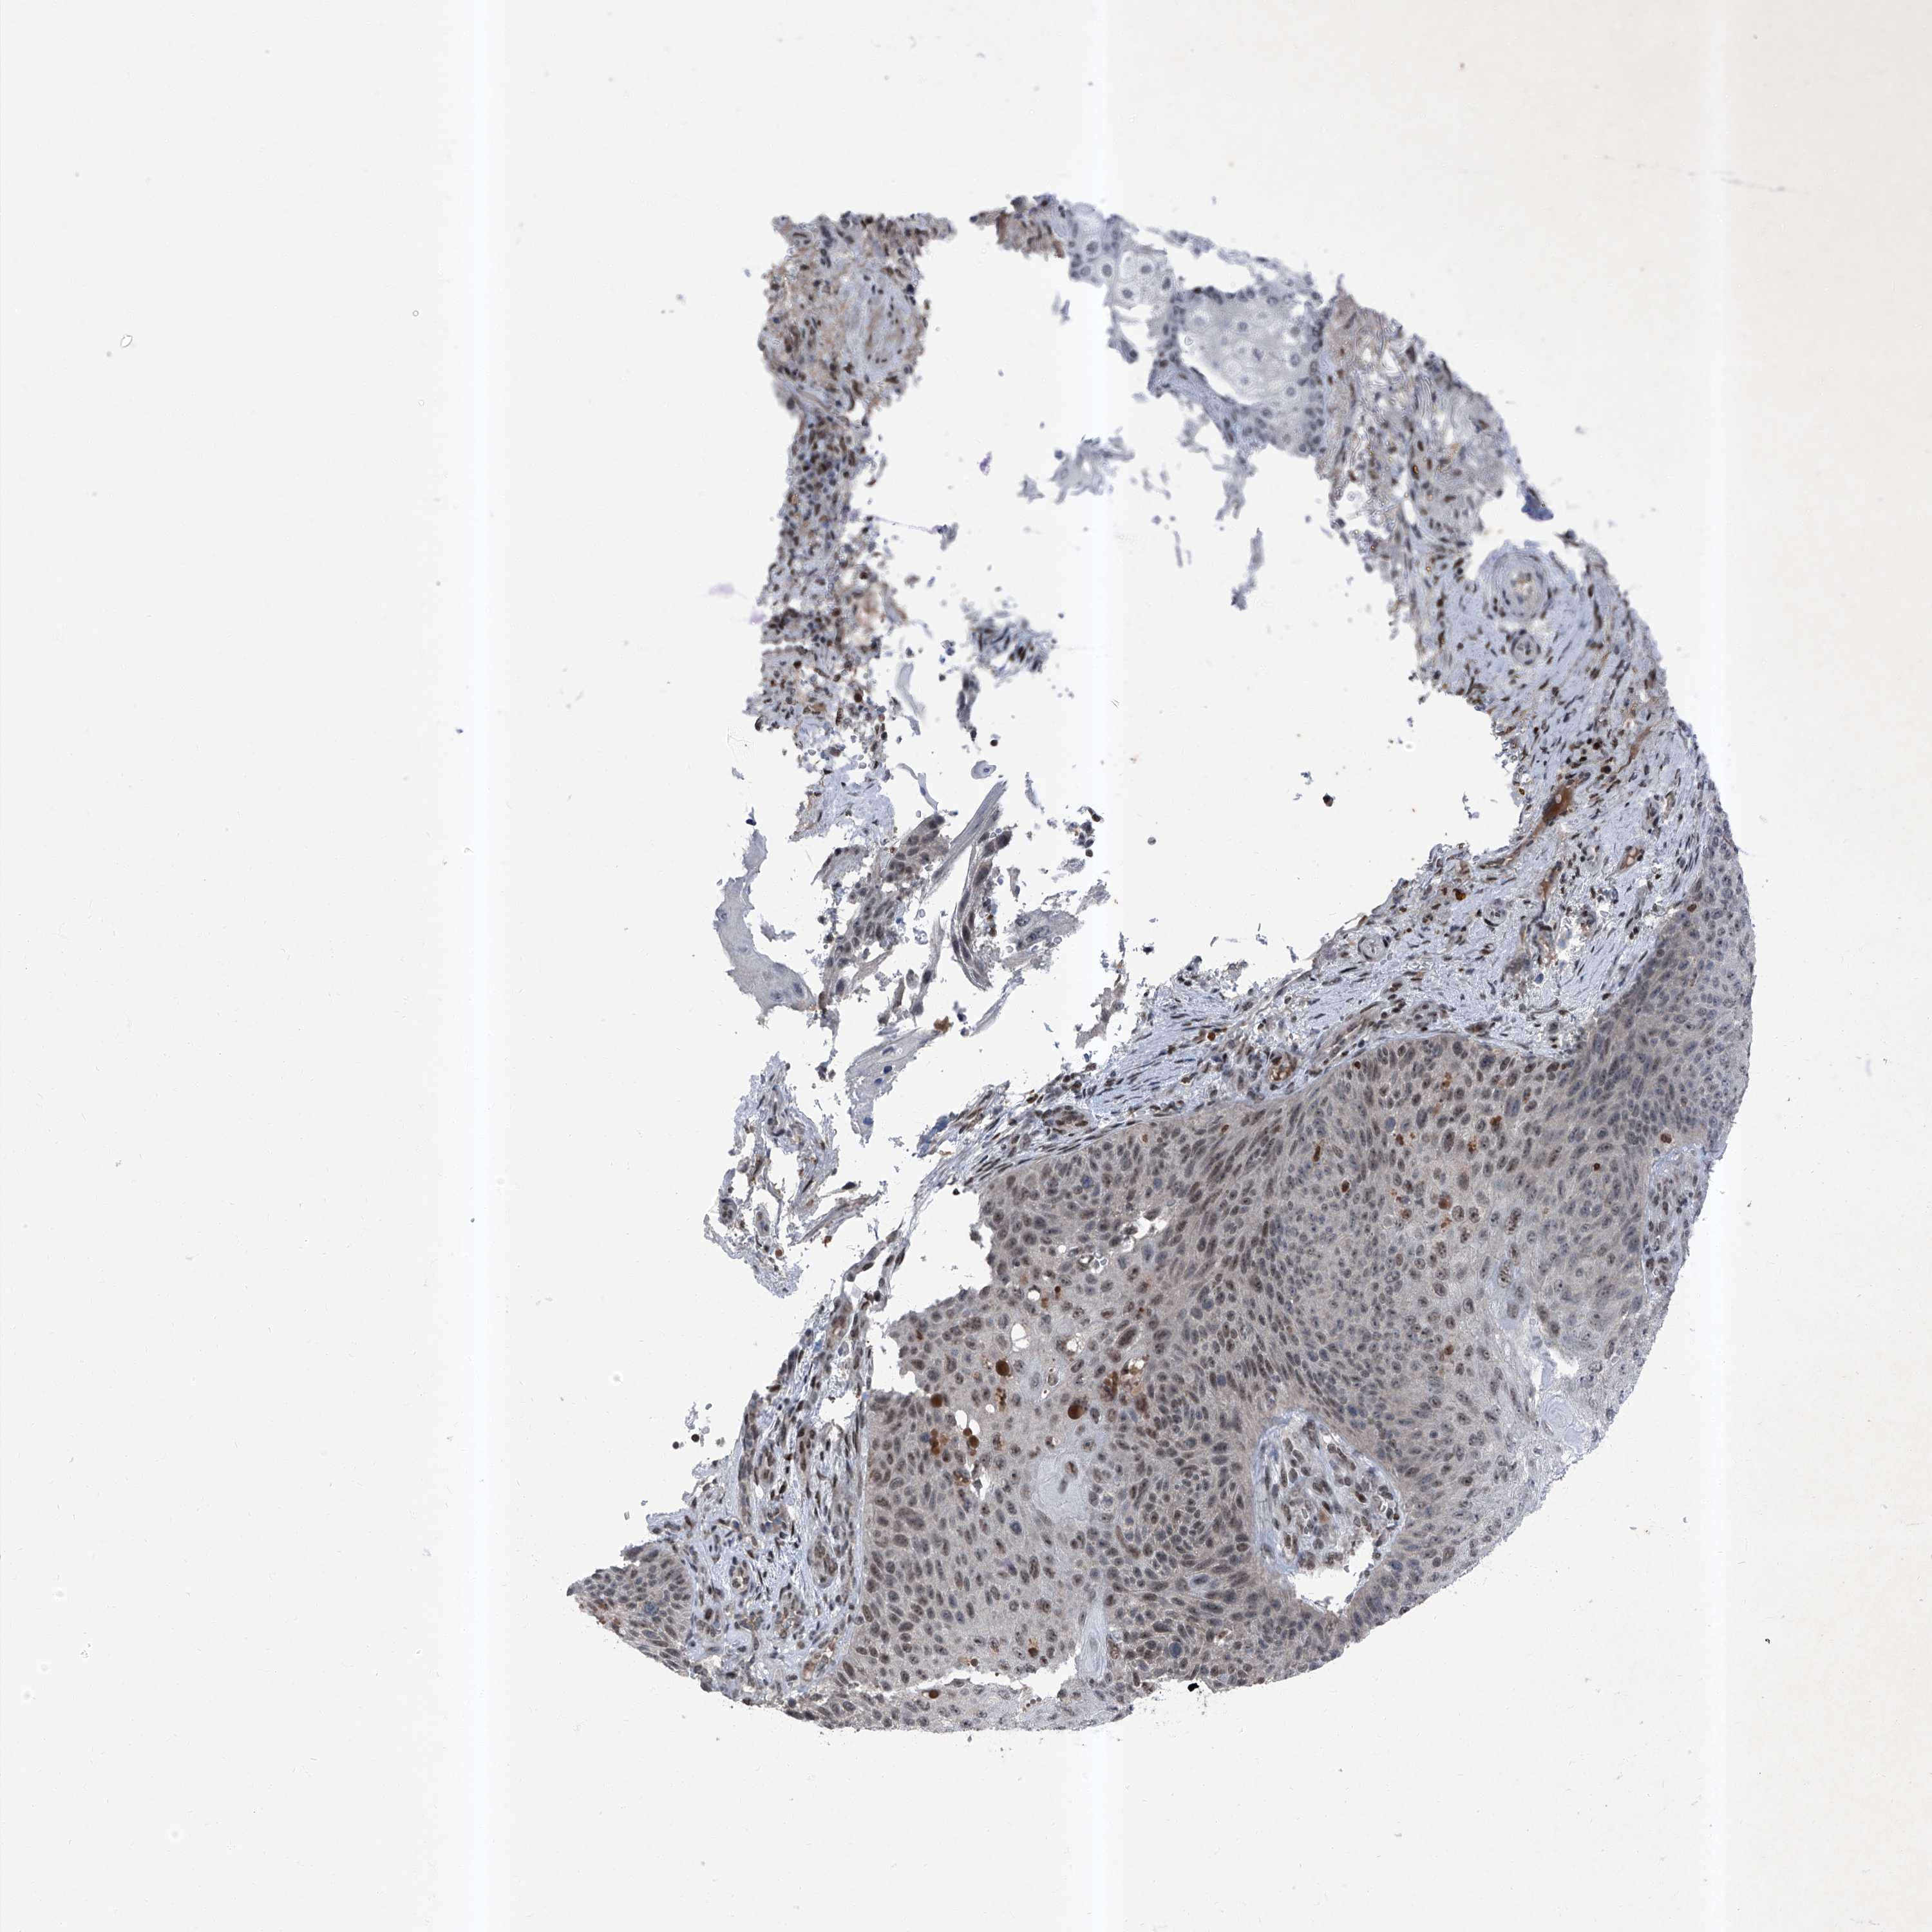

SKIN CANCER - Protein expressioni

A mouse-over function shows sample information and annotation data. Click on an image to view it in a full screen mode. Samples can be filtered based on level of antibody staining by selecting one or several of the following categories: high, medium, low and not detected. The assay and annotation is described here.

Antibody stainingi

Antibody staining in the annotated cell types in the current human tissue is reported as not detected, low, medium, or high, based on conventional immunohistochemistry profiling in selected tissues. This score is based on the combination of the staining intensity and fraction of stained cells.

Each image is clickable and will lead to virtual microscopy that enables deeper exploration of all samples and also displays staining intensity scores, fraction scores and subcellular localization as well as patient and tissue information for each sample.

Antibody HPA030472

Antibody HPA036584

Squamous cell carcinoma, NOS